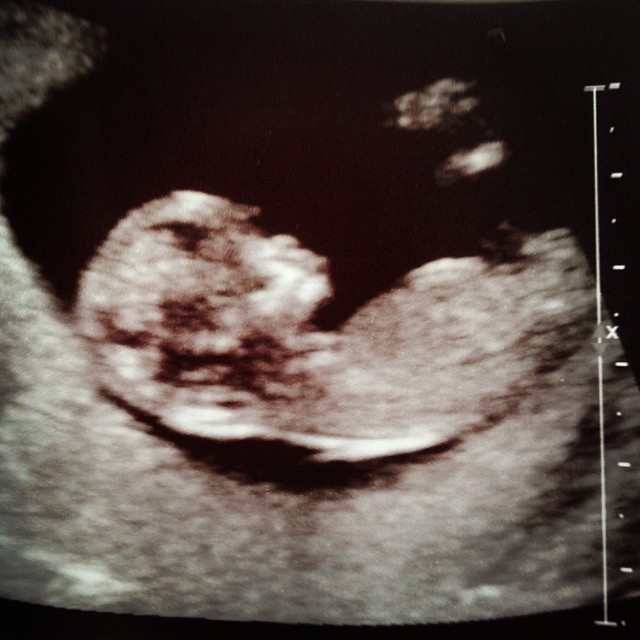

Attachment 16792 12w 2d